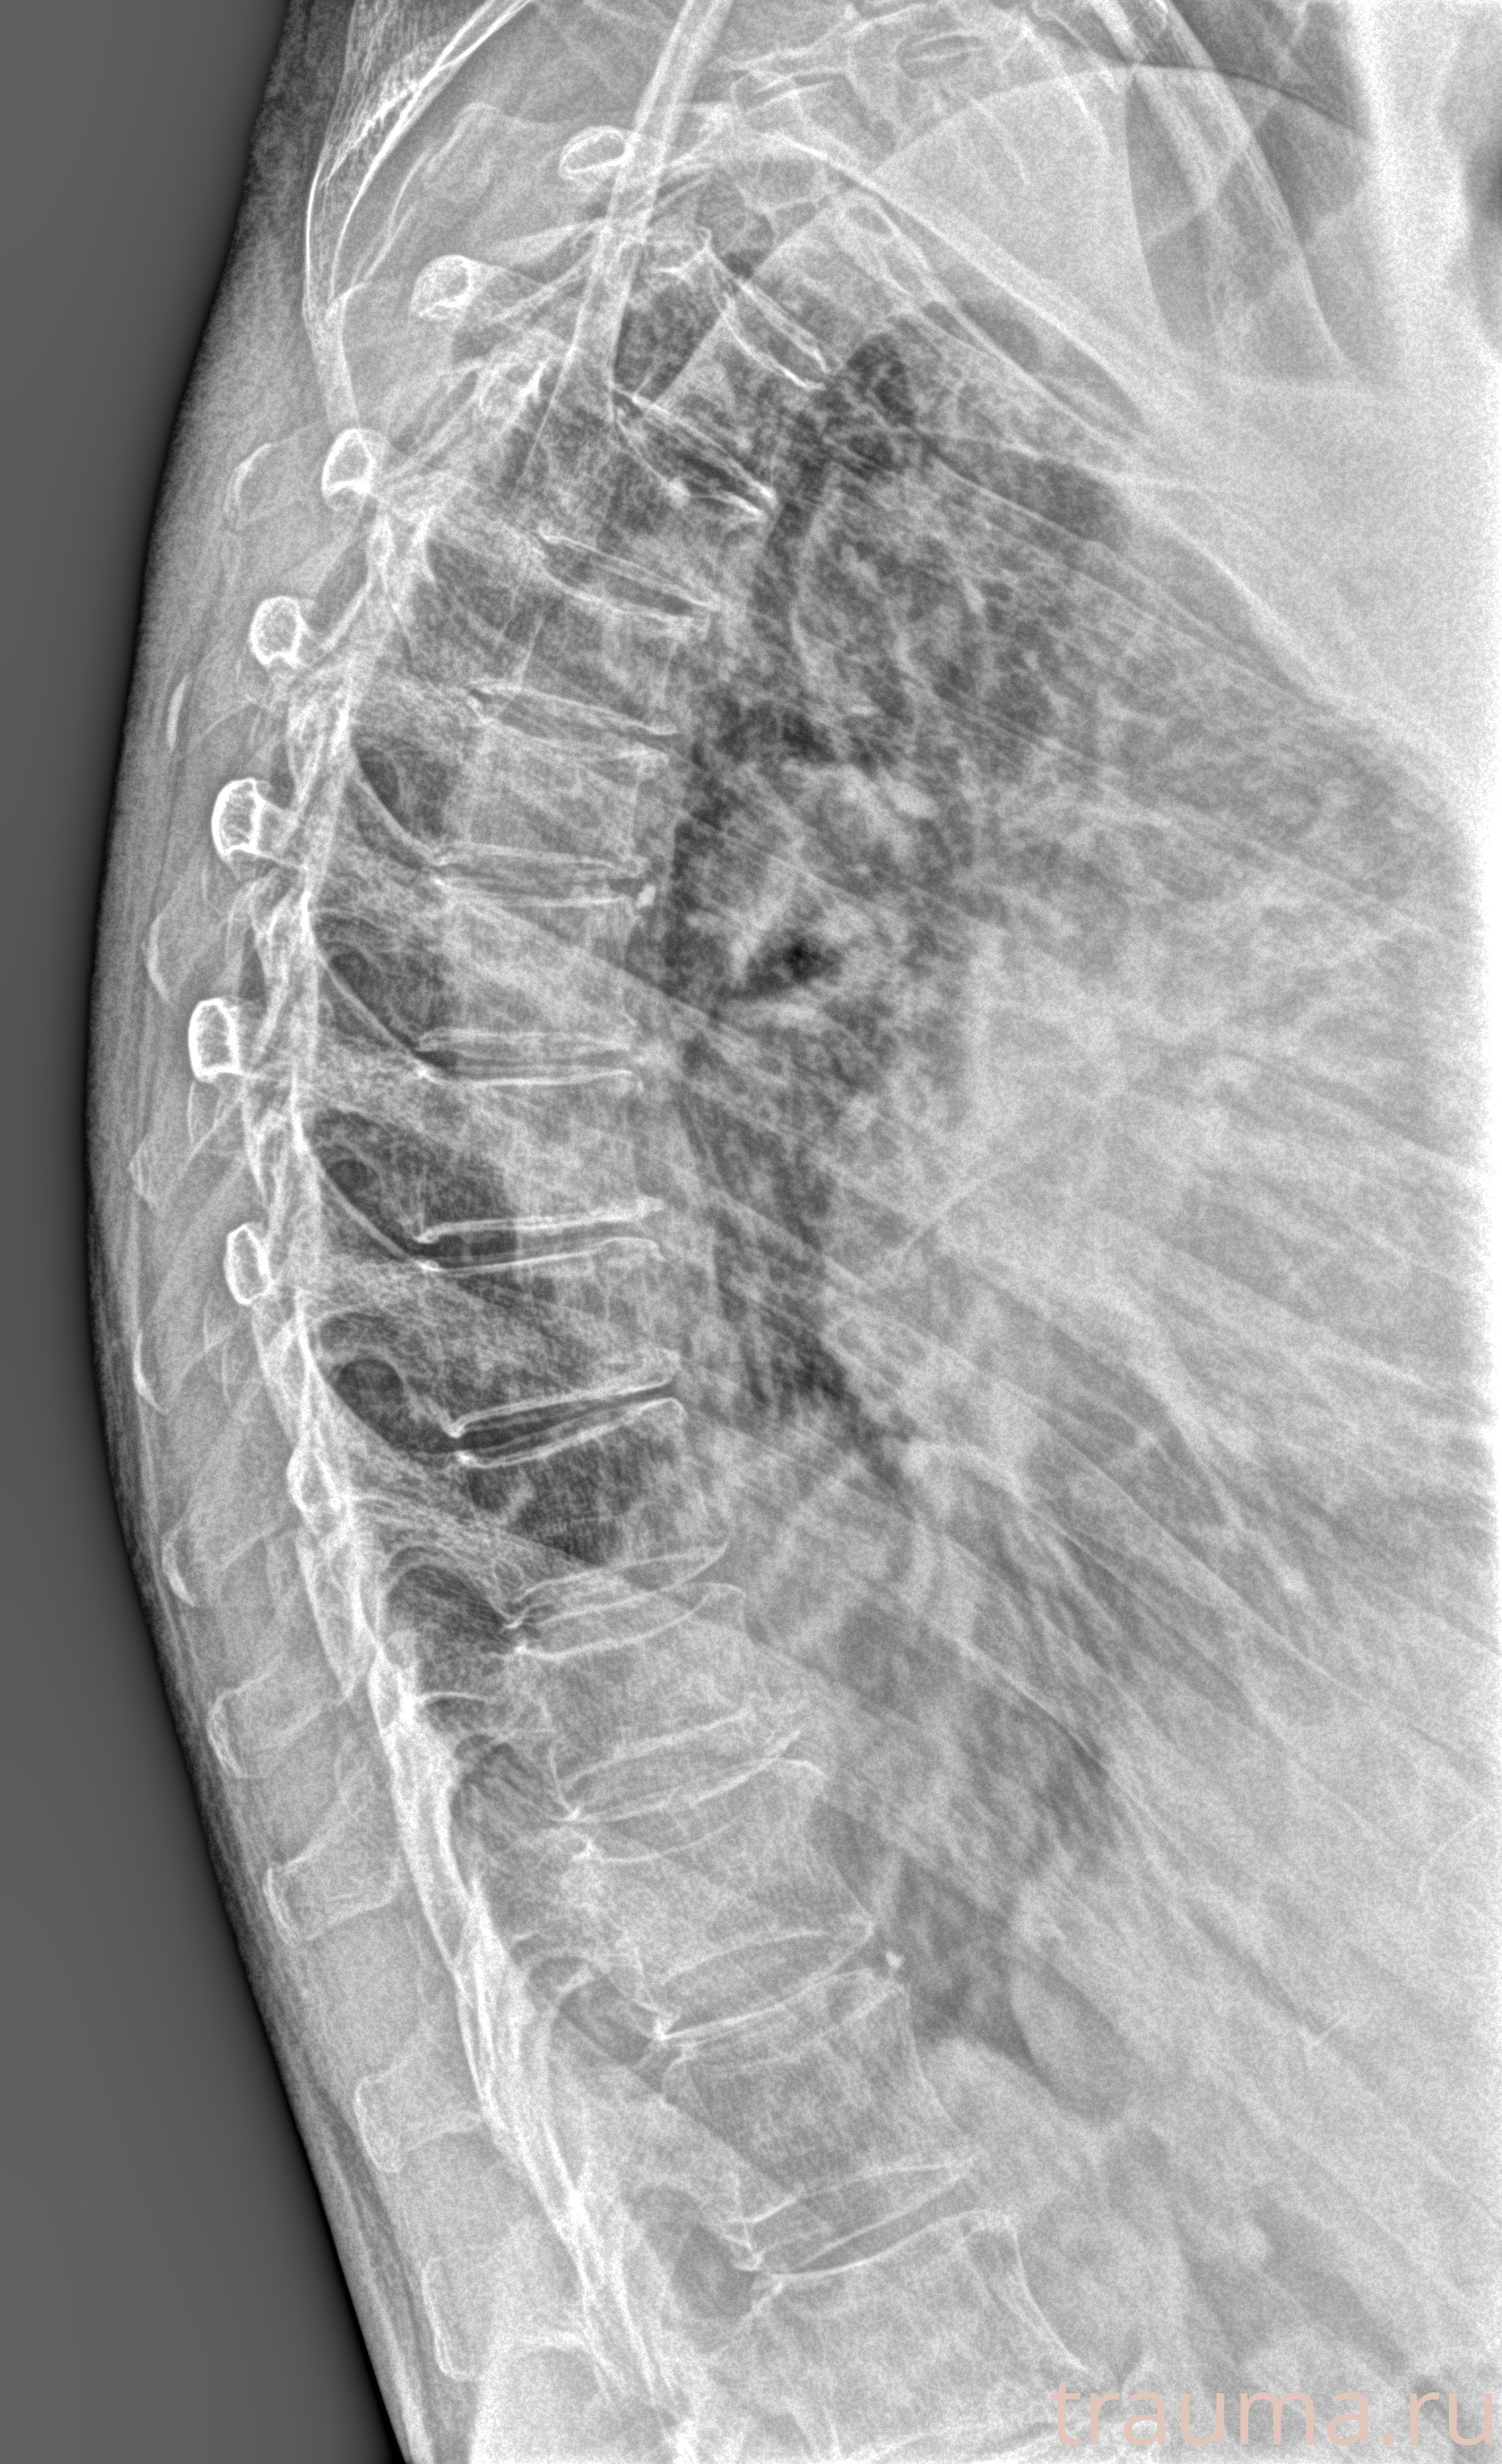

Рентген на дому: по вашему адресу приезжает врач-рентгенолог, травматолог-ортопед с мобильным рентгеновским аппаратом, проводит диагностику травмы или заболевания, делает необходимые рентгенограммы, дает рекомендации по дальнейшему лечению. Получить качественные снимки в домашних условиях возможно благодаря уникальной методике, разработанной МосРентген Центром для института  Склифосовского